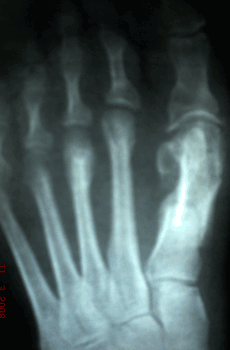

Caso 2: Hallux Valgus del Adulto

Haga click para agrandar las imágenes